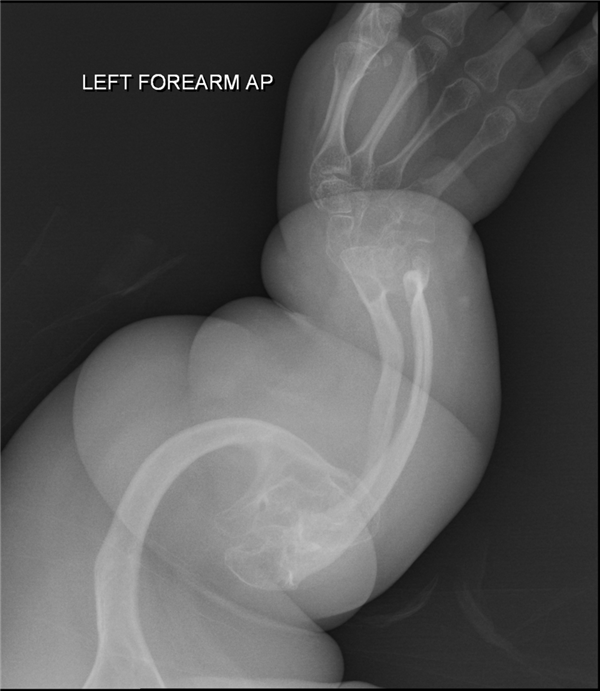

一个4周大的女婴,身上有4处不同程度的骨折,其父母还无法给出合理的解释。 面对这种情况,医生第一时间就提高了警惕,怀疑孩子父母有“虐待孩子”的嫌疑。 在就诊时,不仅强制要求给孩子做全身检查,查看孩子是否存在其他损伤,尤其是大脑。而且,还启动了“虐待”相关的调查流程。 若情况属实,孩子父母将面临严重的刑事指控。 前几日,这对父母在媒体上讲述了这段一波三折的乌龙往事。 其他患者X光片——严重骨折 20